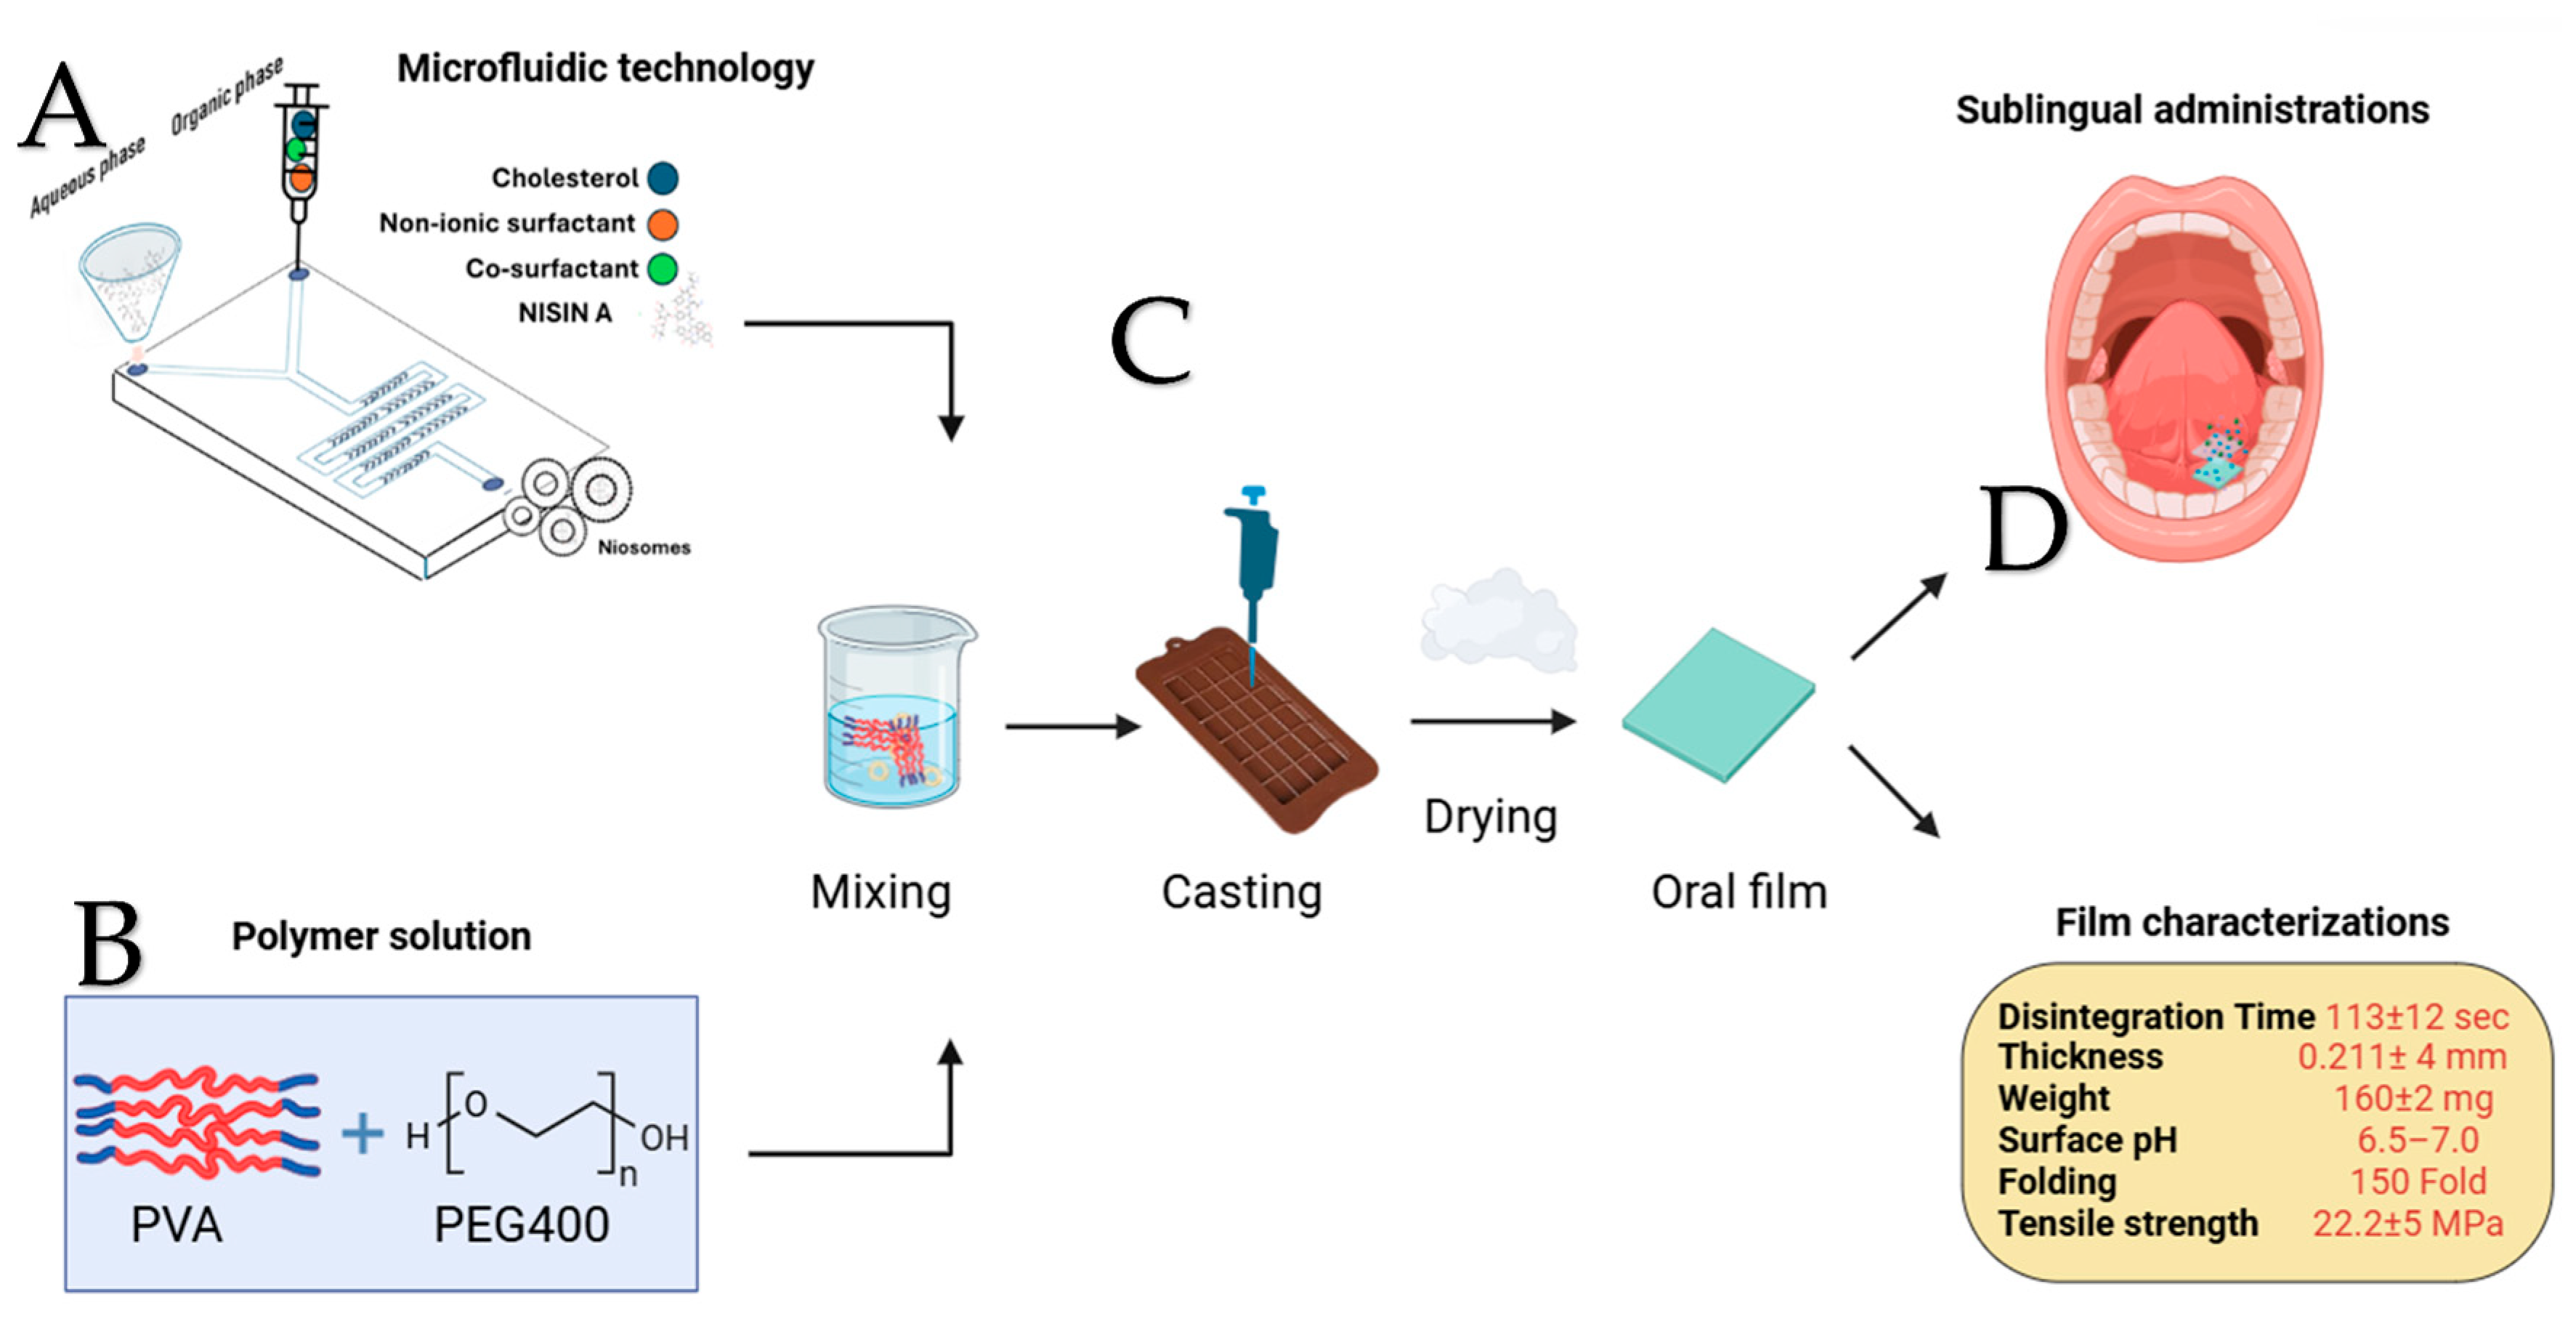

4.2.2. Microfluidic Niosome Synthesis

5.1. Microfluidic Technology

5.3. Film Characterization